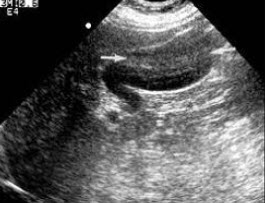

15、单项选择题

根据超声图像所示,该病例为哪型肾积水()

A.菱角型

B.烟斗型